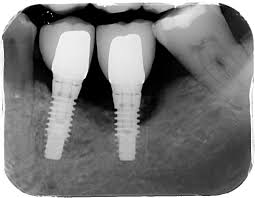

Peri-implant treatment